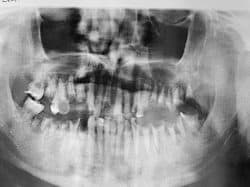

Cases shown are 1) upper and lower arches of bombed-out teeth (included one socket graft using a PGA membrane), 2) erupted thirds, 3) impacted 3rds in a young person.  The PGA membrane is done like a PTFE membrane but does not need to be removed.

This was a “surgical extraction” course but unpredictably had some 3rd molars in the mix.